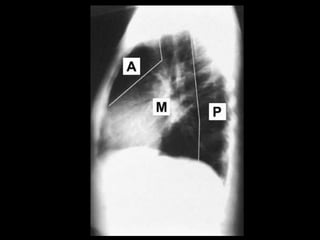

RADIOGRAFIA

• Radiografía normal

• Radiografía patológica

– Ensanchamiento mediastinal

• Técnica radiográfica

• Estructuras normales de tamaño o distribución atípica

• Estructuras vasculares

• Tumores

RADIOGRAFIA • Radiografía normal •Radiografía patológica – Ensanchamiento mediastinal • Técnica radiográfica • Estructuras normales de tamaño o distribución atípica • Estructuras vasculares • Tumores